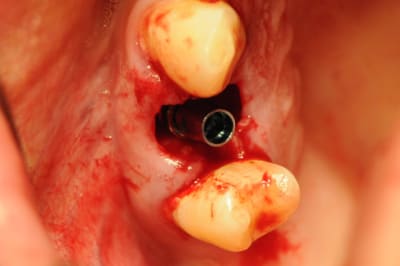

Tiens pour agrémenter! Cet Après midi une extraction implantation. Je n'ai pas oser la mise en charge immédiate si certains l'aurait fait lachez vous.

J'ai fait sauter la table vestibulaire exprès car je ne vois pas comment elle aurait pu etre vascularisée et à part me faire un séquestre osseux et des ennuis j'ai reconstruis.

Regardez les images;

Si certains n'auraient pas extrait argumentez pour traiter en palatin et la felure englobé par le granulome m^me si ce n'est pas mis en évidence sur le scan.

En plus vous voyez le nouvel implant Leone et son indication majeure, c'est vrai que sa mise en place est super aisée, surtout comme celà en palatin.